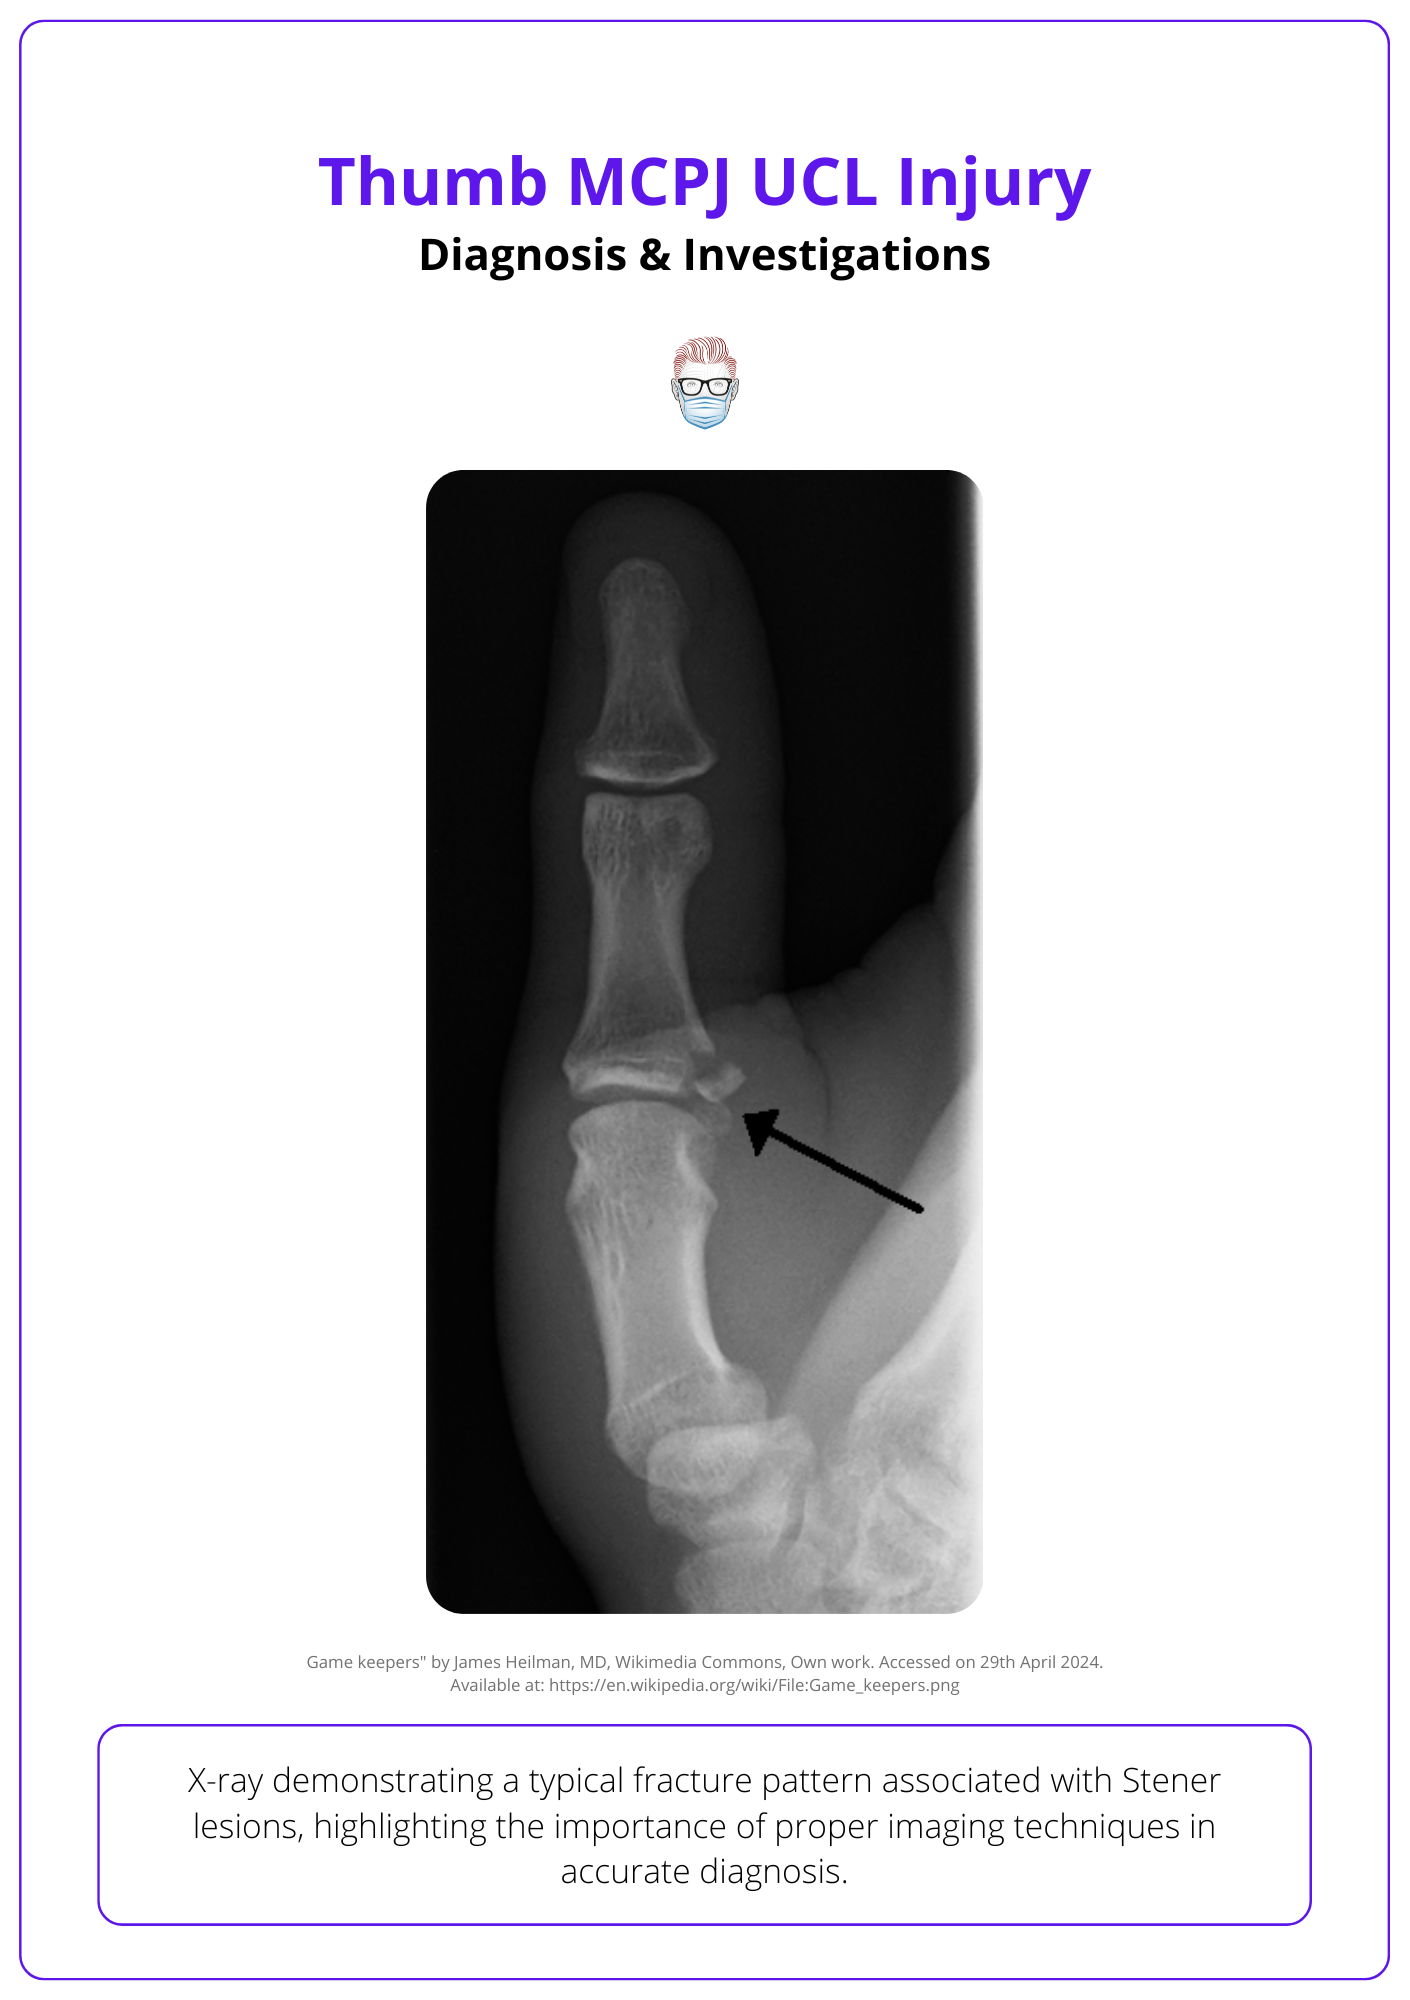

A typical fracture pattern associated with a thumb MCPJ UCL injury is illustrated in the image below.

A Stener lesion occurs when the adductor aponeurosis is interposed between the UCL and MCP joint and prevents a completely avulsed UCL from approximating to its insertion. This requires surgical fixation to regain function.